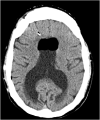

Complications related to Ventriculoperitoneal shunt placement are common, and multiple. Among them blockage and infection. We report a case of 44 years old man admitted to our hospital after an obstruction of his ventriculo-peritoneal shunt by an air bubble that caused behavioral problems and confusion. The patient was operated twice, the last time the puncture point had to be changed. The follow up was marked by a clear clinical improvement. Shunt malfunction continues to be a common neurosurgical problem in patients with shunted hydrocephalus, often leading to frequent and sometimes lengthy hospital stays. This case illustrates the management of this rare situation causing air bubble shunt obstruction.